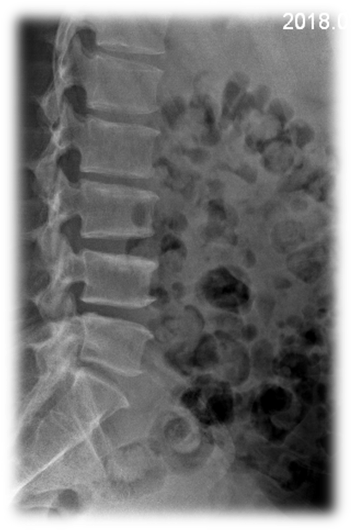

术前 图片4